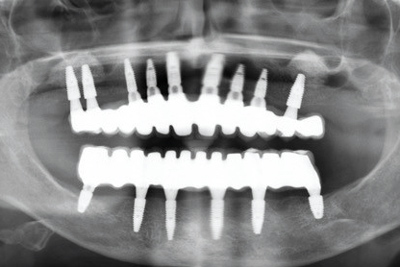

10/11 - The final OPG of the case after sinus lift and implantation

Sinus lift with maxresorb® inject - Dr. E. Valdimarsson

11/11 - OPG control one year after sinus lift and implantation